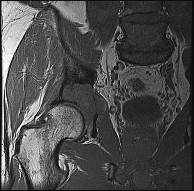

This patient has a dedifferentiated liposarcoma within a preexisting atypical lipomatous tumor. The imaging demonstrates a large fatty mass with increased internal septations proximally (the atypical lipomatous tumor) and a solid enhancing mass distally (the dedifferentiated portion). A biopsy reveals a high-grade liposarcoma. The other diagnostic responses do not reflect sarcomatous transformation of the lesion.

Surgical treatment of a high-grade sarcoma involves wide surgical resection. Radiation decreases local recurrence but does not clearly influence overall survival. The role of chemotherapy in high-grade soft-tissue sarcomas remains investigational; there is a modest (8%-15%) associated improvement in overall survival.

Intramuscular lipomas and atypical lipomatous tumors are treated with marginal resection alone. Radiation therapy for soft-tissue sarcomas may be given before or after surgery. When administered before surgery, patients have a higher wound complication rate but better long-term function attributable to lower rates of lymphedema, fibrosis, and contractures.